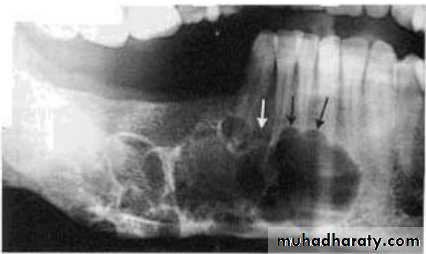

• 2.Position in the jaws:

• - Epicenter of the lesion is above the mandibular canal-odontogenic in origin .

• - Epicenter -below lDC- non odontogenic

Cystic ameloblastoma displaced IDC (odontogenic origin)

Epicenter coronal to tooth

(odontogenic epithelium )

• A lesion (developmental salivary gland

• defect) below the IAC

• (non- odontogenic origin).